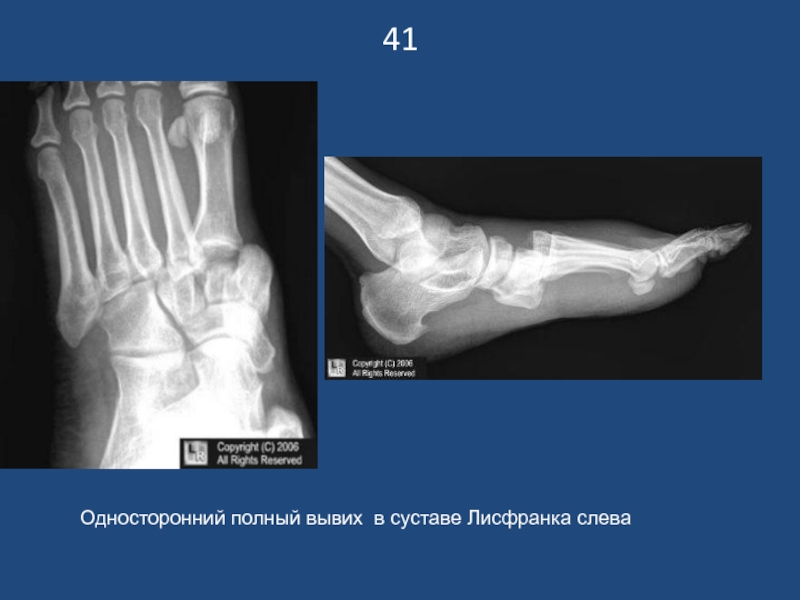

Слайд 4241

Односторонний полный вывих в суставе Лисфранка слева

41Односторонний полный вывих в суставе Лисфранка слева